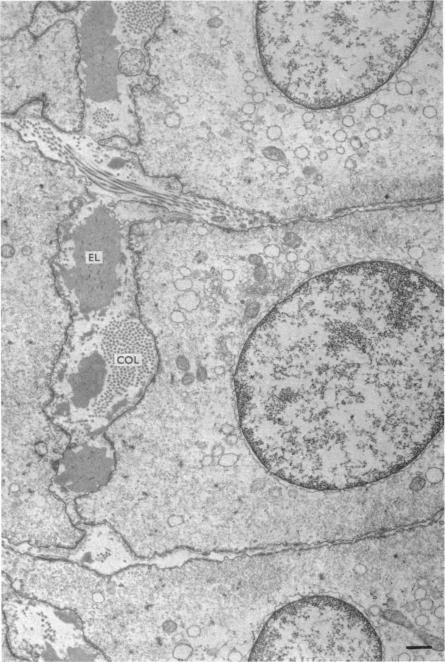

1. The water content, extracellular ((60)CoEDTA) space, ionic composition and ultrastructure of several mammalian smooth muscles were studied after incubation in solutions of varying ionic compositions and osmolarities.2. Substitution of KCl for NaCl resulted in an increase in cell water, K and Cl, accompanied by little change in total wet weight. This was due to a reduction in the extracellular space.3. Changes in extracellular osmolarity produced a wider range of cell volumes in high KCl solutions than in Krebs. The addition of 29-58 mM sucrose to high KCl prevented the swelling.4. Electron microscopy of smooth muscle swollen in high KCl solution revealed light (less electron opaque than normal) fibres of increased diameter, reduction in extracellular space, and nuclear swelling. The normal thick filament lattice was destroyed in swollen, osmium-fixed smooth muscles.5. The ultrastructural changes ascribed to swelling were absent in smooth muscles, (a) depolarized in high K(2)SO(4) solutions, (b) in high KCl solutions with 29-58 mM sucrose, and (c) returned to normal Krebs solution for recovery from swelling.6. Smooth muscles incubated in high KCl (swollen) and high K(2)SO(4) (unswollen) exhibited similar contractile responses, suggesting the filament lattice was intact until fixation, and that the contractile mechanism can operate over a relatively wide range of actin to myosin separations.7. Shrinkage of smooth muscles in high KCl solutions made hypertonic with the addition of 10% sucrose was accompanied by an aggregation of the thick filaments.8. The cell water of fixed taenia coli was reduced (a) by incubation in hypertonic solution followed by fixation in normal glutaraldehyde, or (b) by fixation of normal tissue in hypertonic glutaraldehyde. Osmotic responses during aldehyde fixation may be a source of artifact in the visualization of the normal filament lattice.

4. 在高KCl溶液中肿胀的平滑肌的电子显微镜检查显示,纤维变亮(电子密度低于正常)、直径增加、细胞外空间减少和核肿胀。在肿胀的、经锇固定的平滑肌中,正常的粗肌丝晶格被破坏。